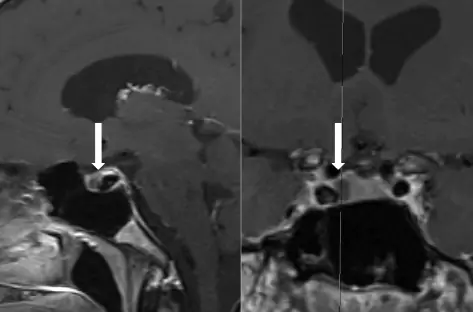

МРТ гипофиза. T1 контрастные изображения. Левое изображение: сагиттальный вид. Правое изображение: корональный вид. Белая стрелка указывает на кистозную структуру в гипофизе

У 47-летнего мужчины был диагностирован СН в возрасте 35 лет. Сообщалось, что МРТ головного мозга 1, 5 Тесла в другой больнице была нормальной. Пациент попал под наше лечение в 2011 году. Приступы и патология головной боли были совместимы с первичным диагнозом CCH в соответствии с критериями Международного общества головной боли (ICHD-3 beta, 3.1.2) (2). Пациент описал приступы строго правосторонней орбито-височной головной боли, связанной с ипсилатеральным разрывом и заложенностью носа. Приступы продолжались от 20 до 60 минут, с частотой до 4 атак в день, часто включая одну атаку ночью. Наиболее последовательным триггером было употребление алкоголя. Подкожные инъекции суматриптана по 6 мг были очень эффективны при прерывании приступов, вдыхаемого кислорода с высоким расходом не было. Несмотря на различные профилактические процедуры (верапамил до 480 мг / день, литий до 800 мг / день, топирамат до 400 мг / день), пациент никогда не был дольше 1 месяца без приступов. К февралю 2014 года у пациента развилась непрерывная межпериодическая боль, ипсилатеральная к правосторонним приступам СН. В этот момент он находился под постоянным лечением верапамилом (максимальная переносимая доза 560 мг / день) в течение 6 месяцев, лишь незначительно влияя на частоту приступов. Тест на индометацин (до 225 мг / день перорально) был отрицательным. Из-за изменения характера головной боли мы решили провести новую МРТ головного мозга, которая показала кистозную структуру в гипофизе (рис. 1). Дифференциальный диагноз был между расщелиной кисты Ратке или кистозной аденомой. Функциональные тесты на гипофиз (PFT) вернулись к норме, за исключением повышенного уровня пролактина (68, 4 мкг / л, нормальные значения 4-17 мкг / л) и низкого уровня свободного тестостерона (4, 44 нг / дл, нормальные значения 6-25 нг / дл). Это может быть связано с гиперпролактинемией, вызванной верапамилом, или пролактиномой. Не было никакой галактореи, гинекомастии или эректильной дисфункции (но он признал низкое либидо), и поля зрения были полны. Пациент не хотел прекращать лечение верапамилом, так как боялся увеличения частоты кластерных приступов. Пациент был направлен к эндокринологу, который начал принимать карберолин, агонист допамина, в дозе 0, 25 мг два раза в неделю. Через несколько недель после начала лечения каберголином приступы СН полностью прекратились, и верапамил можно было успешно остановить. Уровень сывороточного пролактина и тестостерона нормализовался. Повторная МРТ в октябре 2015 года продемонстрировала 30-процентное уменьшение размера кистозного поражения гипофиза. В настоящее время пациент находится на лечении карберголином в течение 1, 5 лет, и головные боли кластера с тех пор не возвращались, и уровни пролактина оставались в пределах нормы. Интересно, что пациент сообщает, что испытывает новый тип односторонних лобно-височных приступов головной боли примерно с 6 месяцев. Эти приступы более легкие и кратковременные (секунды), а боль довольно колющая. Нет связанных черепных вегетативных симптомов. Эти приступы не приводят к инвалидности, и пациент не нуждается в лечении для них. Мы обозначили эти вероятные кратковременные односторонние приступы нервной боли (ICHDI-3, 3.5.3) в данном контексте.